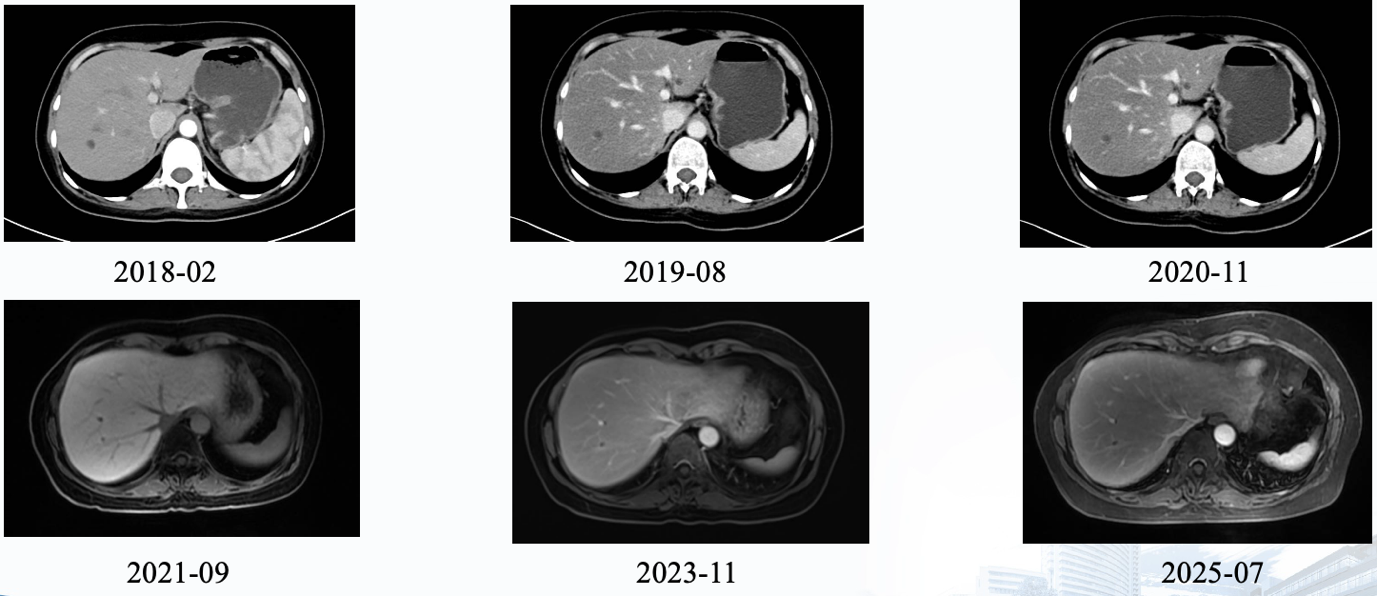

理论的终点是实践。江苏省人民医院华一佳医生分享的一例跨度长达9年的绝经前晚期乳腺癌病例,生动诠释了慢病化管理的精髓。

该患者为49岁Luminal B型乳腺癌女性,2012年术后,2016年出现多发骨、肝转移。在经历一线吉西他滨及紫杉醇化疗不耐受或仅获稳后,患者自2017年起接受了CDK4/6抑制剂(哌柏西利)联合内分泌治疗的维持方案。这一组合展现了持久疗效,虽然中途因注射硬结将氟维司群调整为口服依西美坦,但截至汇报时,患者PFS已超过9年,病灶持续稳定,且保持了极高的生活质量。

在潘跃银教授的主持下,专家团围绕该病例进行了深入剖析。针对维持治疗策略,Hope Rugo教授与Michael Gnant教授一致认为,在疗效极佳且耐受良好的情况下,应坚持现有方案,不宜轻易停药或降阶梯,除非出现无法耐受的毒性。王涛教授则提出了更具探索性的观点,认为随着肿瘤负荷降低至极低水平,未来或许可以尝试“做减法”,以进一步减轻患者的长期药物负担。郝春芳教授补充道,如果患者在长期治疗中出现骨髓抑制等不良反应,可以考虑下调CDK4/6抑制剂的剂量,以最小有效剂量进行维持,这更符合临床实际。

针对患者存在的骨转移和肝转移病灶,是否需要引入局部治疗(如放疗、消融等),Hope Rugo教授持审慎态度。她认为,目前的证据并不支持在广泛转移的情况下通过局部治疗改变最终结局,反而可能增加治疗毒性或并发症。她强调,除非是为了缓解症状(如骨痛),否则应以系统治疗为主。王涛教授表示认同,指出晚期乳腺癌的治疗应是全身与局部的有机结合,但在该病例中,全身控制良好,局部治疗并非当务之急。